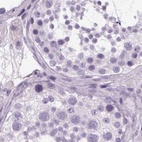

Immunohistochemical staining of human cerebral cortex, liver, pituitary gland and testis using Anti-POMC antibody HPA063644 (A) shows similar protein distribution across tissues to independent antibody HPA046135 (B).